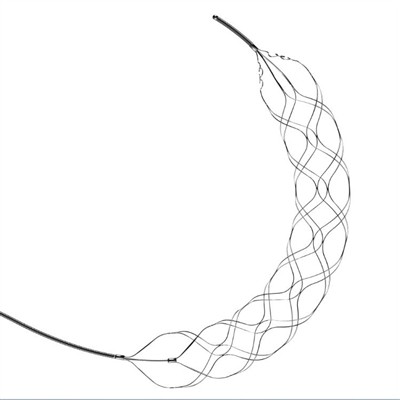

Avantajele pentru Trombectomie Stent RetrieverÎn ultimii ani, stent retrievers de trombectomie au apărut ca o opțiune de tratament extrem de eficientă pentru pacienții care suferă de accident vascular cerebral ischemic acut. Această procedură min

Tipuri de dispozitive de trombectomieAccidentul vascular cerebral este o cauză majoră de dizabilitate și deces la nivel mondial. În ultimii ani, dezvoltarea dispozitivelor de trombectomie pentru tratamentul AVC ischemic acut a revoluțion

Coiling endovascular pentru tratarea accidentului vascular cerebral hemoragicÎnfăşurarea endovasculară este o procedură care implică trecerea unui fir subţire printr-o arteră din zona inghinală şi ghidarea acesteia până la locul sângerării din creier. Odată ce sârma este la lo